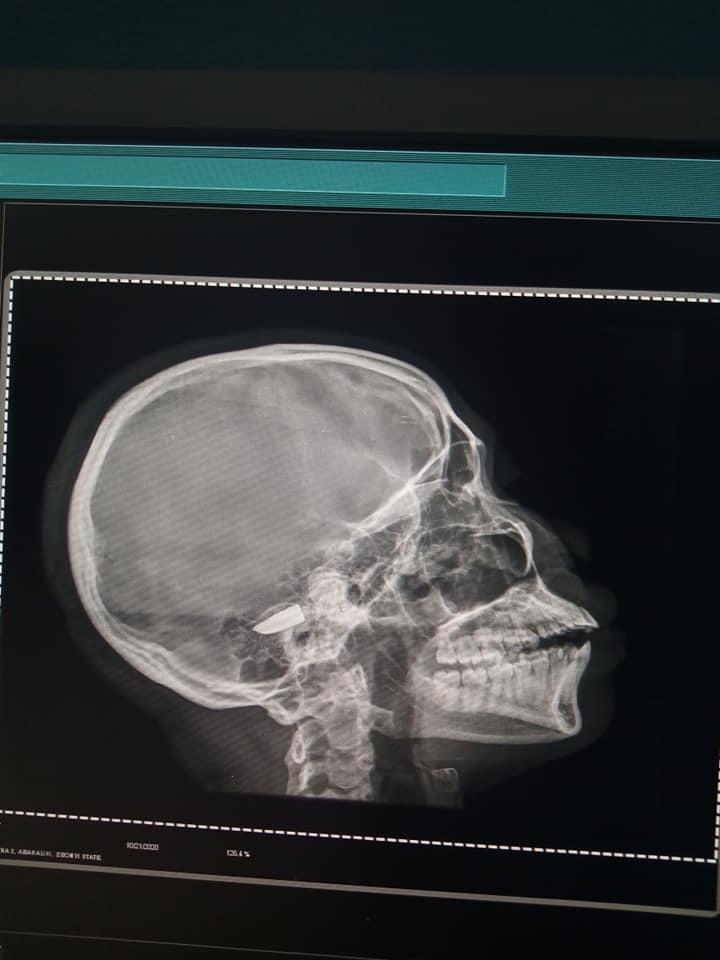

She calls her sister a fighter who while during her surgery, was still joking and smiling. Sharing photos of her sister and an X-Ray scan of the bullet in her head, Valentina wrote,

Meet my kid sister a fighter Girl lived five days with a Bullet in her head, playing Joking and smiling. This God sew her through. If u Don’t believe in this God I Pity you he sew my family. Through this hard days And we came out smiling With joy overflow. Favour Your name keep fighting for You. The God of favour came Through the right time. Iloveyoukiddoh.??❤❤